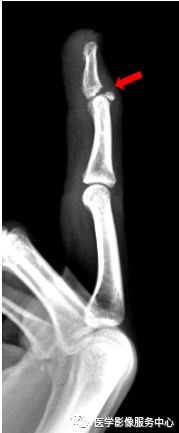

右手骨折 手術- 橈骨遠位端骨折は骨折の中でも、比較的多く見られる骨折です。 しかし、「橈骨遠位端骨折とうこつえんいたんこっせつ」と聞いてもピンとこない方がほとんどだと思います。 では、橈骨とはどこの骨で、どんな骨折なのでしょうか? 上の骨折部位 1.中手骨骨幹部 (こっかんぶ) 骨折 原因: 中手骨の中央部を骨幹部といい、この部での骨折です。 物が手の甲に当たるなど、強い力が直接骨に加わったり、手をひねる力が加わったりして発生します(図2、3)。 症状:

手首の骨折の治療法 手首の骨折の治療は、自然治癒力によって癒合させるのが基本です。 応急処置 応急処置は症状の悪化を防ぎます。骨折部がズレると治療行程が増えて、治療期間が長引きます。 まずは副木で手首の関節を固定します。 良いほうの右手の骨と比べて見ても、 ほぼ変わりないくらい骨折部分がきれいに治っていることがわかります。 この時点で、しっかり治ったことを確認して、 通院終了となりました。骨折部位によって骨の転位方向が変わります。 a, 基部:浅指屈筋腱付着部よりも 近位 で折れた場合は 屈曲変形(背側凸) が起こりやすく(図41) b, 中央:浅指屈筋腱付着部よりも 遠位 で折れた場合は 伸展変形(掌側凸) の変形になりやすい(図42) c, 遠位:受傷機転により変形方向が